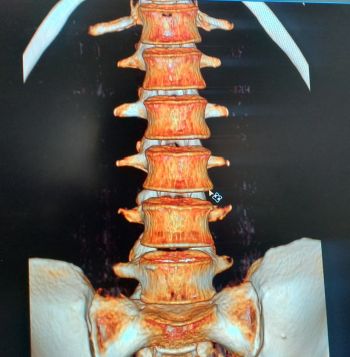

Il utilise les rayons X. C'est grâce à la rotation du système de détecteurs que le scanner permet la création d'images 2D et 3D, voire même 4D pour certains examens (scanner cardiaque).